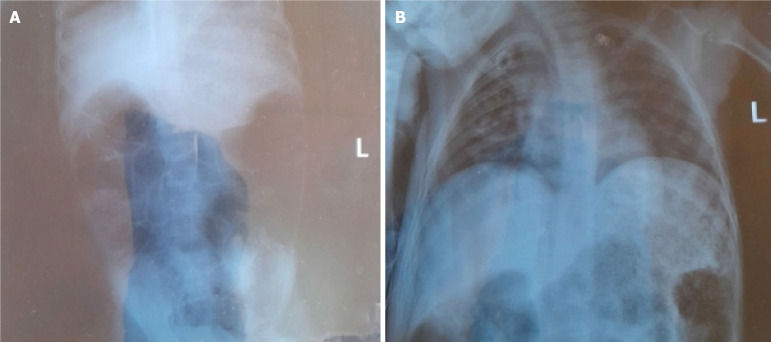

Case summary: We report a case of a 5-year-old boy who presented with altered sensorium and abdominal distension following suspected OP exposure. Physical examination and imaging revealed features of intestinal obstruction and neurological deficits. He was managed with atropine, pralidoxime, and other supportive measures and had a successful recovery. Paralytic ileus is an atypical complication of acute OP poisoning. The resultant intestinal obstruction manifests as cholinergic overactivity, leading to bowel dysmotility. This case emphasizes the need for awareness and prompt management of such atypical presentations, especially in the pediatric population.